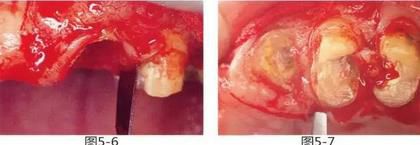

圖5-6,7

使用手術(shù)刀、7號牙齦刀、11號牙齦刀、咬骨鉗,盡可能將牙根周圍的軟組織進行整體切除。